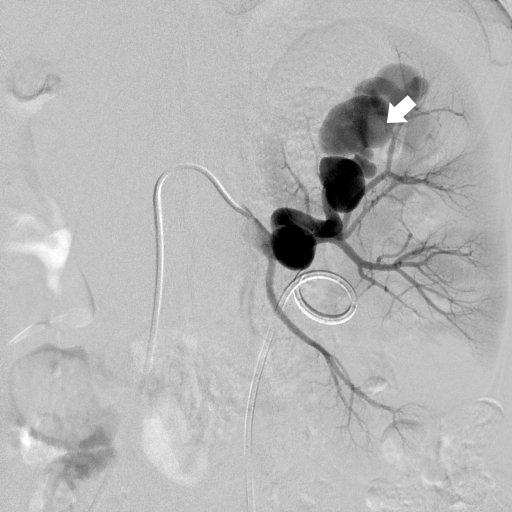

主に足の付け根にある動脈にカテーテルを挿入し、肝臓や腎臓、胆嚢、腸などの臓器の血管の状態と流れを検査します。動脈瘤、動脈奇形、肝臓がん、腎臓がん、膵臓がん、外傷性出血など、さまざまな疾病の検査に用いられ、経皮的リザーバー留置術・動脈瘤や血管奇形への動脈塞栓・腫瘍への動脈塞栓、化学塞栓療法・出血への塞栓術・血管形成術等カテーテルによる治療を行います。低侵襲で選択的に治療を行いますので、正常の臓器を温存できる特徴もあります。